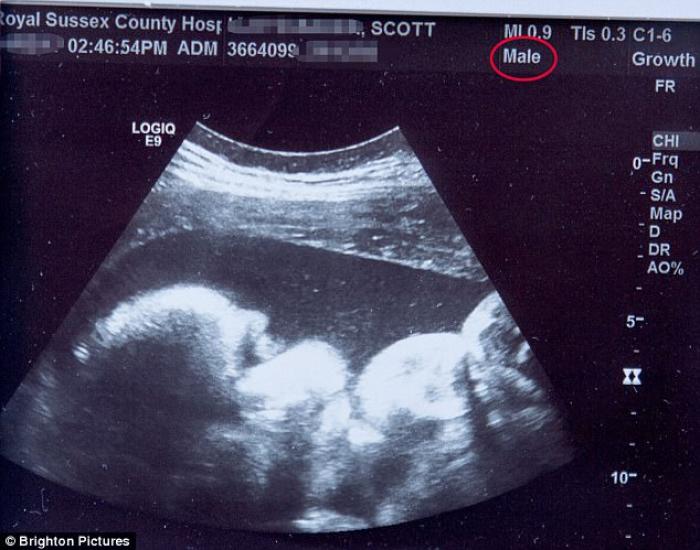

Acesta este PRIMUL bărbat care a NĂSCUT! Scott Parker din Marea Britanie a adus pe lume o fetiță! FOTO

Si-a dorit un copil, iar de când a nascut, a început tranzitia.